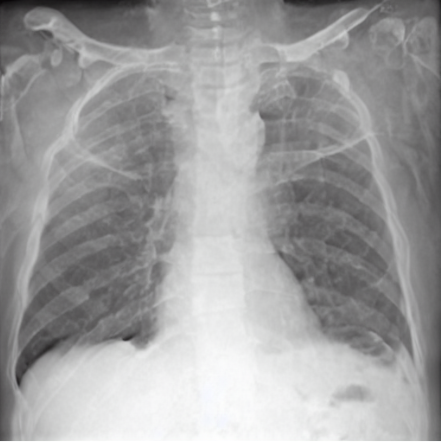

4.1 Qualitative Evaluation of Healthy Counterpart Generation

Example images from the disease COVID-19 Radiography Database and their generative healthy counterparts are given in figure 2. The images on the far left are instances of the lung opacity class from the real images in the dataset. The images in the middle column are examples of the generated healthy counterfactuals obtained via latent space diffusion, with RadBERT-guided textual-conditioning via a conditional prompt “normal chest x-ray”. A total of 75 diffusion inference steps are used with image conditioning strength=0.85 and guidance scale=7.5. (The former indicates the level of constraint on changes to the original input image and the latter is the weight given to the textual encoder conditioning in the generation of the image, ranging over [0,1] and [0,9], respectively).

Side-by-side inspection of the generated healthy counterfactuals (as per fig. 2) suggests that, as required, only minimal perturbation is made to the original image with respect to healthy pixels -i.e. localized image sites without structural medical defects. (In the top row, the medical structural defect in the original image is due to a lung opacity, and characterized via a relatively complex interaction between the imaging modality and subject manifesting as ‘gaps’ in the corresponding portions of the lung scan). The healthy/non-healthy discrepancy maps in all of these cases are obtained via masked subtraction of the original image from the generated image (the ground truth segmentation masks correspond to the broad area of interest –i.e. the complete lung). The generated healthy tissue is thus a subset of the mask and is shown in the final column of fig. 2 for the respective cases.

In the context of a VANT-GAN[20]-based approach, this highlighted material constitutes the diagnostic counterfactual visual attribution, i.e. the selection of material relevant to the diagnosis of the unhealthy condition. Healthy counterfactual generation was performed for the complete datasets in the three unhealthy classes, i.e Lung opacity, Viral Pneumonia and COVID, examples of which are given in fig. 3 for the three classes (all of the generated healthy counterfactuals from this experiment can be found on https://huggingface.co/ammaradeel/diffusionVA). Visual inspection indicates that the generated counterfactuals are, in general, visually plausible with minimal perturbation made to the unhealthy image overall. Moreover, the healthy counterpart generation does not appear to unnecessarily affect aspects of the images unrelated to the medical condition, the model selectively making changes to the unhealthy regions in a structurally plausible manner, e.g. generating missing portions of the lung without generating extraneous lung material where it would be expected to normally exist (e.g. in the abdominal cavity).